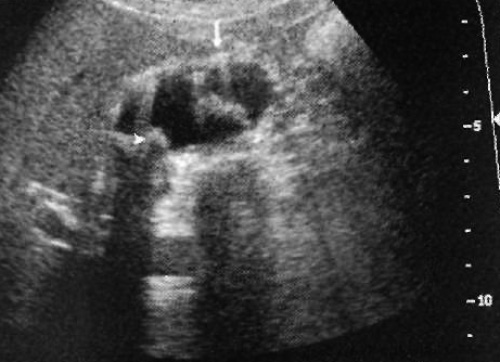

Застойная желчь формируется из билирубината кальция и кристаллов холестерина, которые содержаться в желчи. Ультразвуковая картина застойной желчи характеризуется эхом умеренной интенсивности. Застой желчи, обусловленный перееданием, обструкцией желчевыводящих протоков на уровне желчного пузыря, пузырного протока или общего желчного протока, является основной причиной образования застойной желчи (фото 10). Застой желчи (билиарный сладж) может указывать на какое-либо сопутствующее заболевание, однако не является специфическим признаком.

Фото 10. Застой желчи (билиарный сладж). А – УЗИ в продольной проекции, пациент в положении лежа на спине. В – УЗИ в продольной проекции того же пациента в положении лежа на левом боку. Ультразвуковая картина демонстрирует подвижный эхогенный застой желчи, форма которого меняется при перемене положения тела пациента